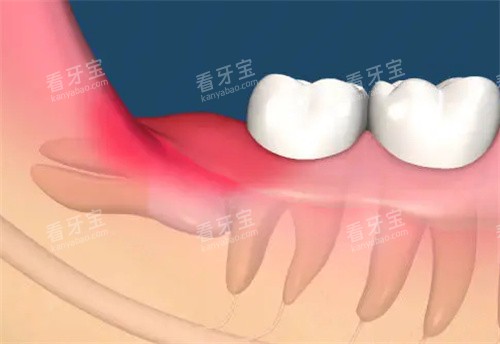

反复发作的智齿冠周炎(每年发作≥3次)。

智齿本身龋坏且已波及牙髓。

阻生智齿压迫邻牙导致牙根吸收。